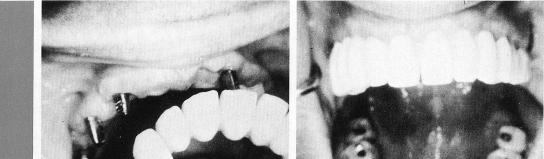

The single-tooth bladevent here acts as the anterior abutment for a four-unit restoration, preventing the sacrifice of the more anterior crowns for inclusion in the restoration. The single-tooth implant is inserted between a second bicuspid, which has undergone root canal therapy, and the cuspid (1,2). A bladevent is also set behind the natural tooth. Thus three abutments (3) provide strong support for a four-unit restoration (4).

2 Maxillary implant abutments provide support for four unit restoration